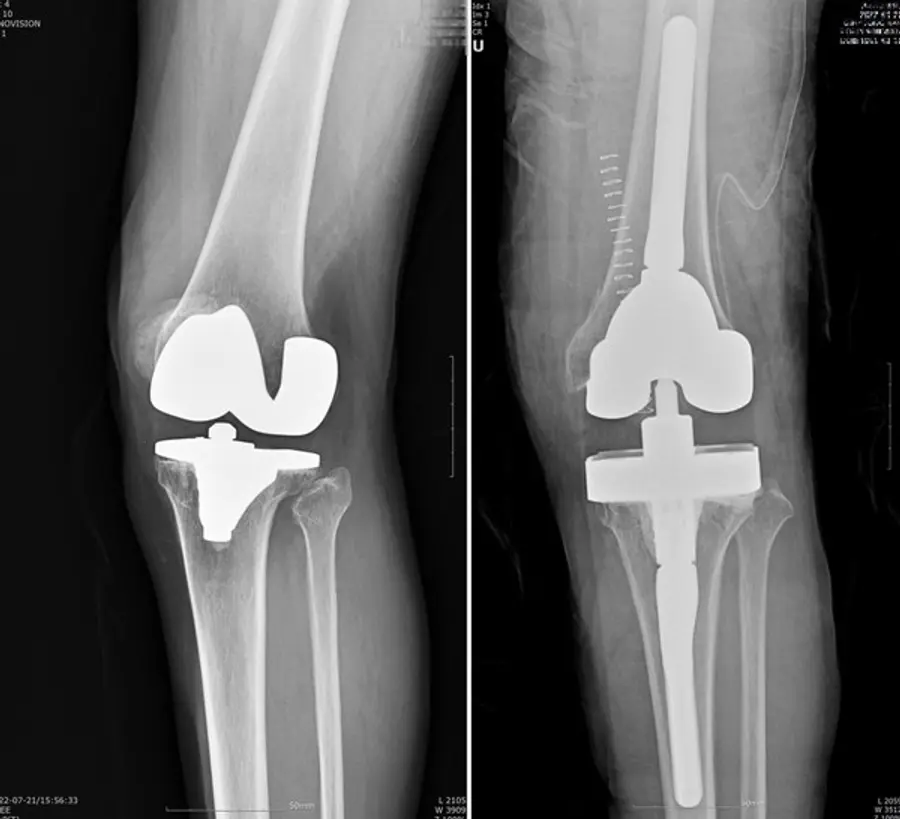

인공관절 재치환술은 A씨처럼 외상으로 인해 문제가 생기거나, 인공관절을 오래 써서 닳아 흔들리거나 염증, 감염 등으로 인해 인공관절이 제 기능을 하지 못하고 통증을 유발하는 경우 시행하게 된다.

인공관절 재치환술은 많은 경우 골 소실 및 연부조직 손상을 동반하기 때문에 수술 자체도 까다롭고 처음 수술보다 결과가 좋지 않은 경우도 있다. 또 대부분 80세 이상의 고령 환자가 많아 만성질환 합병증의 위험도 따른다. 실제 보건복지부 지정 관절전문 연세사랑병원의 통계에 따르면 인공관절 재수술을 받은 환자 809명 중 80세 이상이 16%를 차지했다.